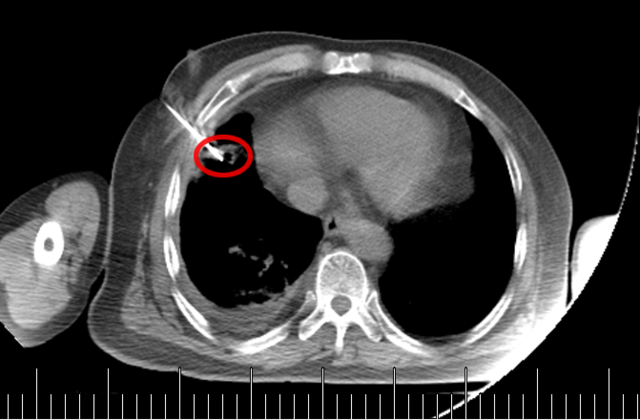

起初,常规思路是做气管镜检查取病理,但完善肺功能检查后发现,老先生有重度阻塞性肺通气功能障碍(相当于呼吸系统 “交通堵塞”),根本耐受不了气管镜。好在这个肿块虽然位置特殊,但体积较大、离胸壁较近 —— 和患者及家属充分沟通后,医生决定采用 “CT 引导下经皮肺穿刺活检”。

它就像一位精准定位的 “远程射手”:在 CT 的 “透视眼” 帮助下,医生能清晰看到肺部病变的位置、大小,以及周围的血管、气管等结构;随后用一根细针,从胸壁皮肤轻轻穿刺进入肺部,直达病变部位,抽取少量组织送检。

这种方式尤其适合深部或微小病灶—— 比如位置藏得深、体积小到 1cm 左右的病灶,CT 引导几乎是实现精准穿刺的唯一选择,能帮医生在不 “大动干戈” 的情况下明确肿瘤身份。